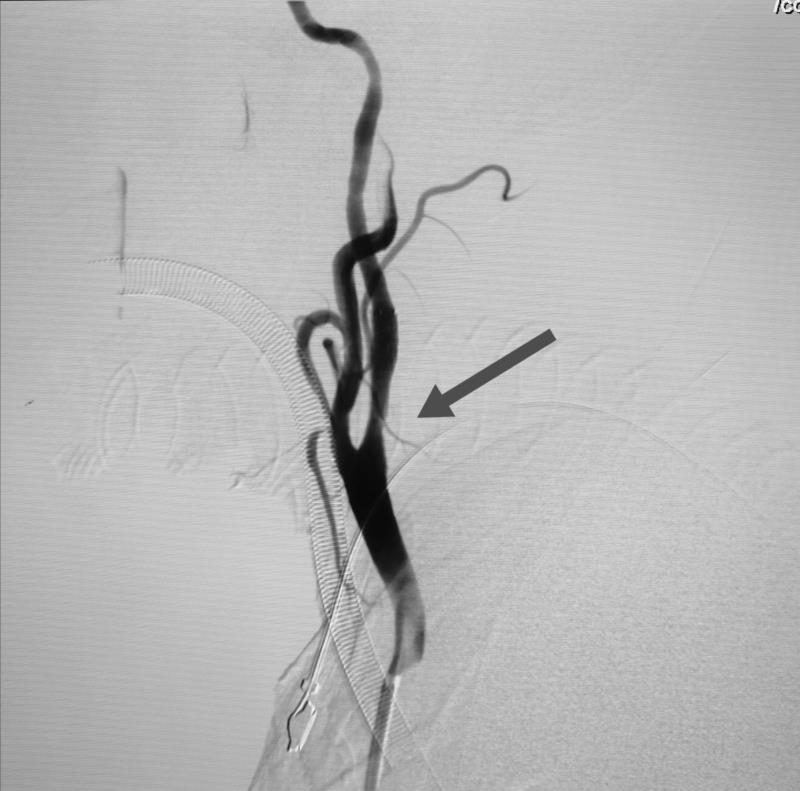

经全脑血管造影术,发现患者右侧椎动脉V4段重度狭窄,正是病灶责任血管,同时发现右侧颈内动脉起始段重度狭窄。患者王某的情况岌岌可危,这两处血管狭窄随时可能闭塞,一旦闭塞,轻则出现严重残疾,完全丧失生活能力,重则很快危及生命,他的椎动脉远端狭窄处介入手术风险异常高,手术过程中很可能发生急性血管破裂或栓塞,形成严重的脑干出血或者梗死,造成死亡。患者右颈内动脉狭窄处于颈动脉窦部,是人体血压和心率的感应器,非常敏感,加之该患者平时就有心率缓慢的情况,术中很有可能心脏停搏造成死亡。

术中,榆林二院心血管介入团队给患者放置心脏临时起搏器,为心脏保驾护航;麻醉科给予患者妥善全麻后,由榆林二院脑科医院神经内科一病区联合神经外科一病区,经过娴熟、精准的操作,顺利完成手术,术中术后未发生任何并发症。

术后,患者头晕、偏盲、视物模糊、行走偏斜、走路不稳,说话笨拙等症状很快得到缓解,生命体征稳定。